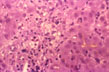

Cytoplasmic cholestasis

Fig 49 - CYTOPLASMIC CHOLESTASIS: Presence of yellow pigment throughout the cytoplasm and not in lysosomes which are pericanalicular. Bilirubin granules will stain green with Hall's method. The hepatocytes may show Mallory bodies, eosinophilicand pseudoxanthomatous degeneration. There may be foci of cell dropout. These changes are most prominent in the central lobular area.